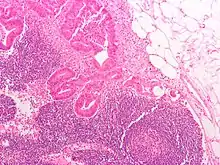

Definitive staging can only be done after surgery and histopathology of colorectal carcinoma. An exception to this principle would be after a colonoscopic polypectomy of a malignant pedunculated polyp with minimal invasion. Preoperative staging of rectal cancers may be done with endoscopic ultrasound. Adjunct staging of metastasis include abdominal ultrasound, MRI, CT, PET scanning, and other imaging studies.